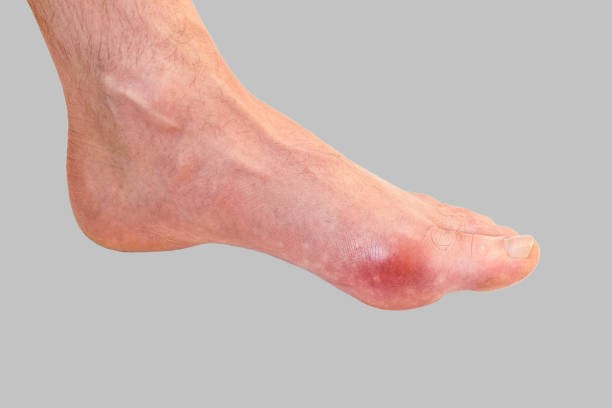

통풍 증상 두 번째는 엄지발가락 통증입니다. 처음에 주로 엄지발가락 근저부 관절에 발병하는데 돌발적인 통증과 함께 붉게 부어오르며 무릎, 손목, 발목, 팔꿈치 등에 발생하기도 합니다.

통풍 증상 네 번째는 급성 통풍 발작인데 엄지발가락, 발목 등 한 곳의 관절이 갑자기 빨갛게 부어오르고 손댈 수 없을 정도로 통증이 심한데 발뒤꿈치, 팔목, 손가락, 귀 등에서 나타나며 급성 통풍성 관절염이라고 부르기도 합니다.